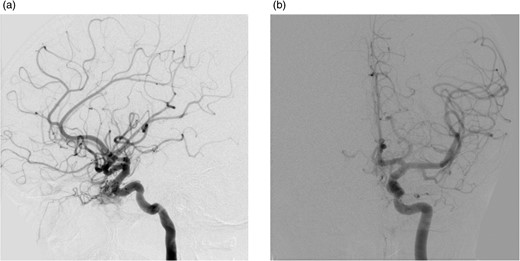

After a discussion that involved the neuroradiology team, neurosurgical team, the patient and her family, a decision was made to proceed with endovascular treatment of the fistula. Following informed consent from the patient's parents, the procedure was performed under general anaesthesia. Axis to the right common femoral artery was achieved with a 6-French micropuncture kit. A 6-French sheath was inserted into the right common femoral vein. A 6-French guide catheter was placed in the left internal jugular bulb. Thereafter, 4-French sheath was placed in the left common femoral vein. Then, a 4-French Weinberg catheter was placed in the left common carotid. A Headway microcatheter was advanced into the cavernous sinus trough the petrosal sinus into the cavernous sinus and subsequently into the dilated ophthalmic vein. Multiple coils were then placed into the ophthalmic vein throughout its course in the orbit back as far as the anterior section of the cavernous sinus. This resulted in near complete occlusion of the fistula. No immediate complications occurred, and the patient woke without any new neurological deficit in recovery (Fig. 3).

(a) and (b) Post-procedural digital subtraction angiogram under general anaesthesia shows no evidence of a residual CCF following coil embolization.

The patient was discharged 3 days later and a follow-up brain magnetic resonance imaging (MRI) was conducted 4 months afterward, which showed some residual proptosis. The superior ophthalmic vein was prominent but clearly less prominent than previous imaging. On a routine outpatient follow-up, her proptosis had significantly improved with reduction of the corneal injection, she reported no headaches and normal vision. A follow-up IR cerebral angiogram was conducted 4 months later that revealed no evidence of a residual CCF.